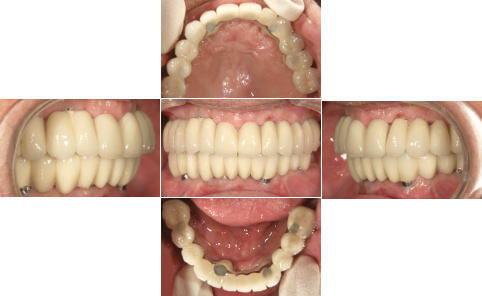

| 関西から通っている患者様です。 近々お嬢様の結婚式があるため、その前に上下共、All-on-4で治療して欲しいと来院されました。 右下親知らずは埋伏歯なので残してあります。 |